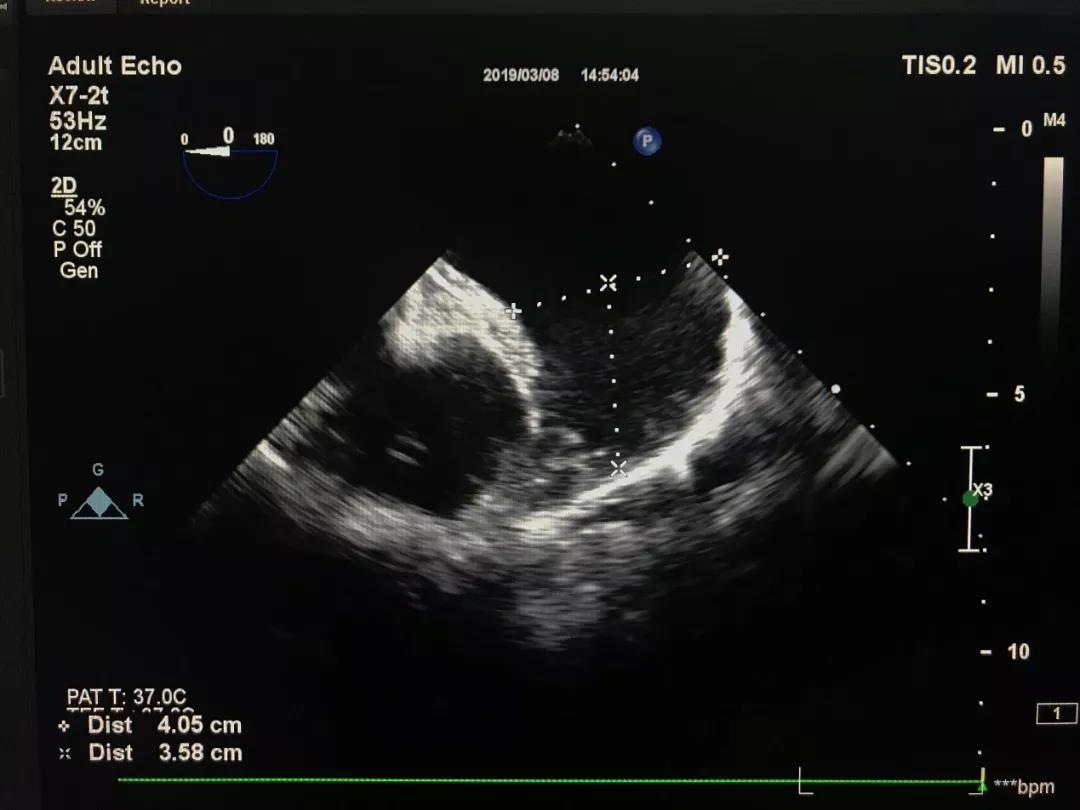

41mm大开口左心耳成功封堵:

心耳开口测量